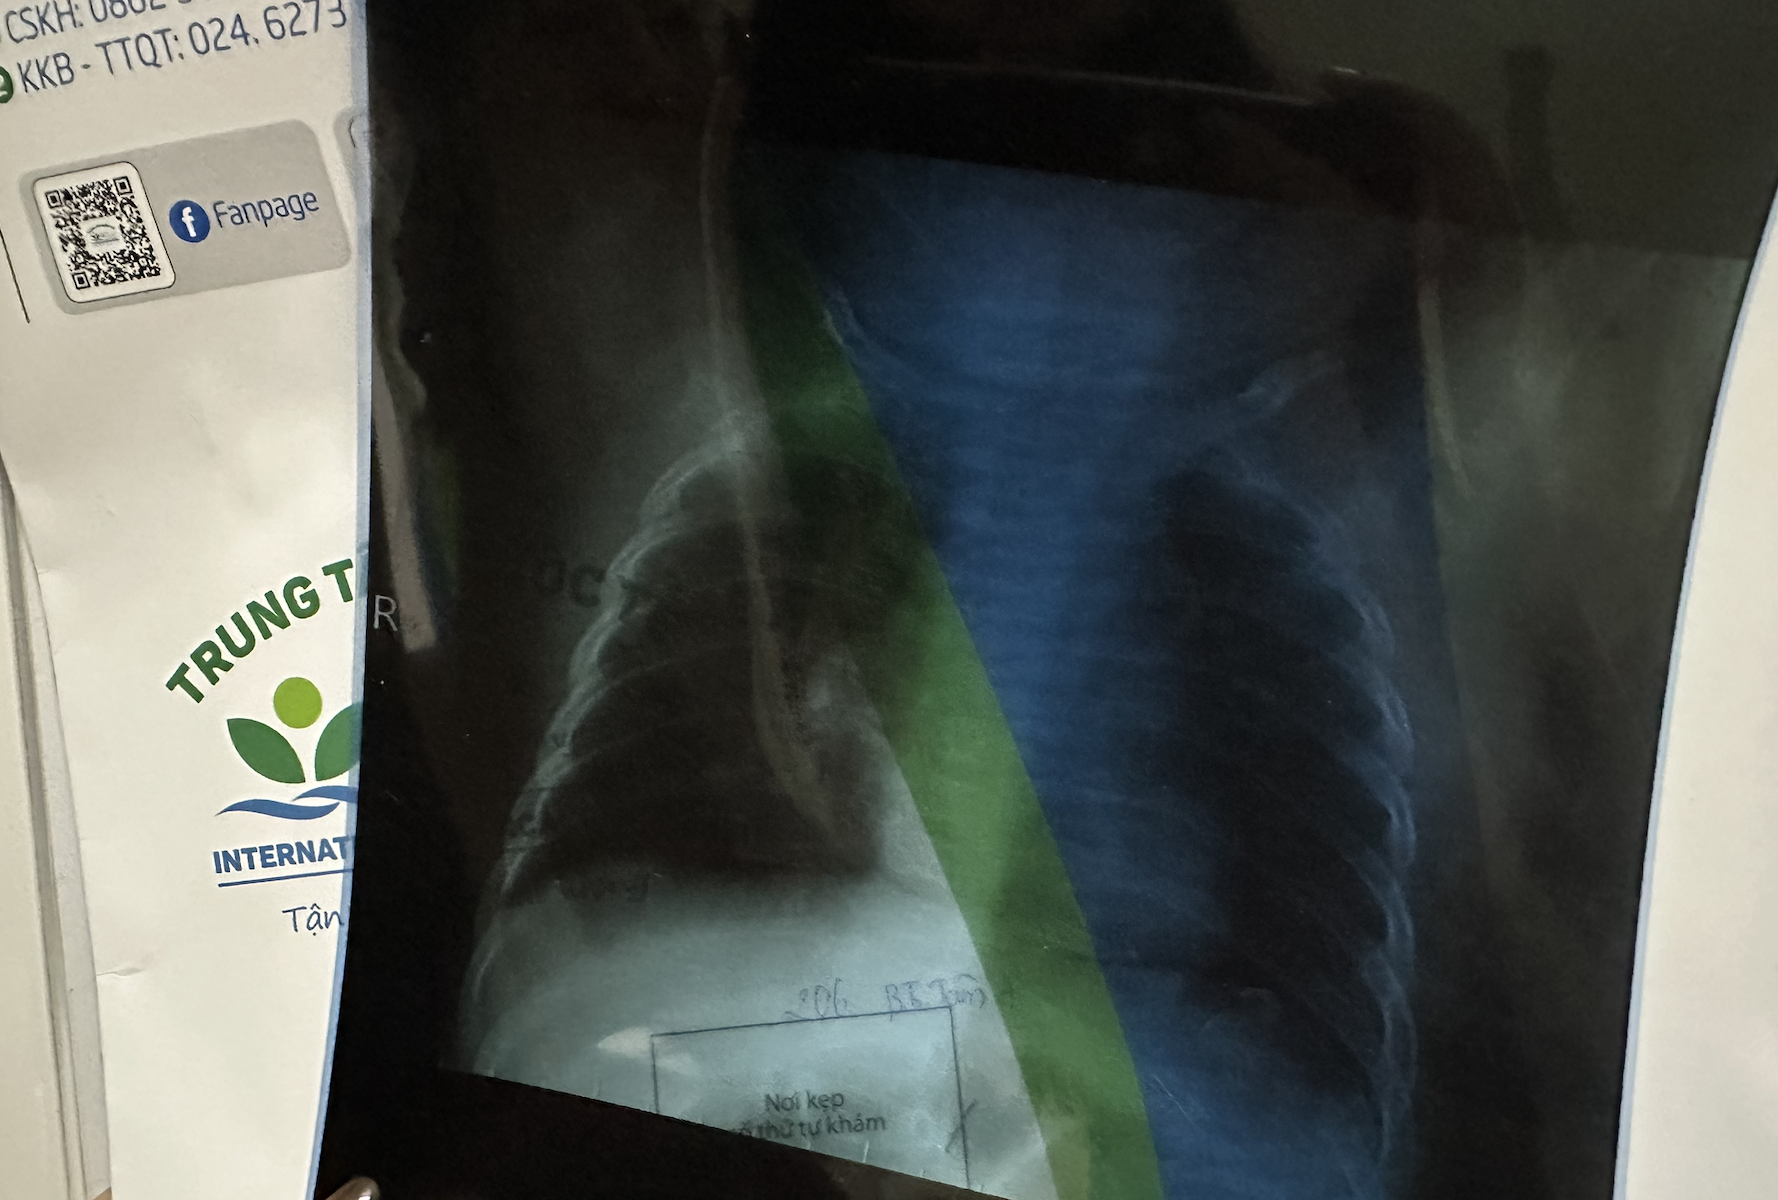

Linh's child's lung X-ray confirmed mild pneumonia, accompanied by otitis media with effusion and a severe cough, necessitating hospitalization. Photo: Provided by interviewee.